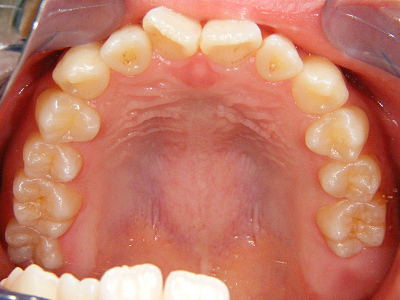

2. 術前上顎

上顎面観でやはり1,1番の翼状捻転および3,3番の捻転が著名。2次成長期を迎える患者様において、上顎歯列弓は劣成長と思われます。